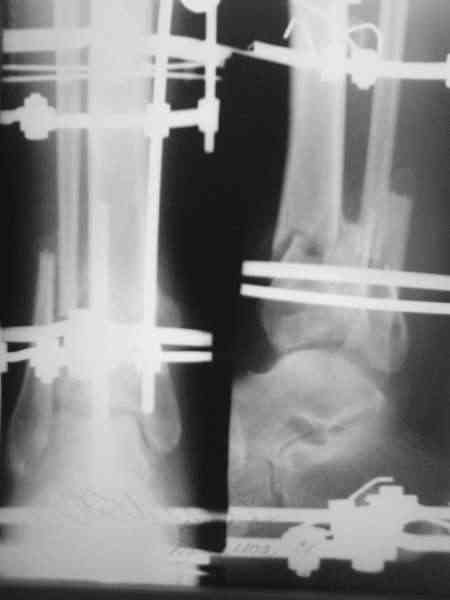

Здравствуйте, коллеги.Сегодня закрыл грануляции расщепленным кожным лоскутом. Начало см здесь Дефект устранил "гофрированием" мягких тканей голени. После этого спицы из дистального отломка удалил. В зоне сближенных отломков идет оссификация. Укорочение голени около 5 см. Что можно предпринять дальше? Тибиализация? Последующее выращивание регенерата в АВФ (в какие сроки оптимально)? Как освободить стопу (и нужно ли сейчас) для разработки в голеностопном суставе? С уважением, Заднепровский Никита Николаевич

Поздравляю с успешным закрытием дефекта голени - гофрирование сработало. Перед свободной кожной пластикой дефекта повторите посев из раны, при обнаружении стрептококков пересадку лучше отложить до полной санации иначе лоскут расплавится. Следующим этапом я бы подумал о перемонтаже аппарата для

создания компрессии в зоне перелома б.б. и проксимальную компактотомию с транспортом костного блока и воостановления длины голени.

Тибиализация это что? Наверное нужно сделать остеотомию(лучше всего косо- поперечную проксильного метафиза пилой Джигли,если получится поднадкостнично). Придется немного перемонтировать аппарат.В ближайщее время,пока не срослась малоберцовая кость, и тянуть не торопясь по 1 мм всутки в 4 подкрутки по 1/4 оборота.Освобождать стопу?!-зачем? Вы убрали спицы из дистального отломка потому что текли. Может имеет смысл провести заново.

Тибиализация малоберцовой кости используется при замещении дефектов большеберцовой кости по методу Илизарова. Спицами с напайками тянут фрагмент малоберцовки к большеберцовке до образования костного блока. В данном случае я расчитываю "укрепить" место перелома фрагментом os fibula который зашел по длине при "гофрировании", так как между отломками рубцовая ткань и расчитывать на истинное сращение здесь, видимо, не придется. Или все же попытаться сдавить отломки tibia с целью раздавливания межотломковых интерпонирующих тканей да начинать "выращивать" остеорегенерат?

Нет, спицы не текли, а появился отек стопы и боли в области сухожилий разгибателей пальцев в конце процесса "гофрирования". Так как репозиции отломков метафиза мне достичь не удалось, то решил убрать их за ненадобностью. Может, попытаться открыто провести репозицию заднего края lag screw задним доступом? Правда время с момента травмы уже 30 дней. Или лучшее враг хорошего? Чем больше занимаюсь этим больным, тем больше вопросов.